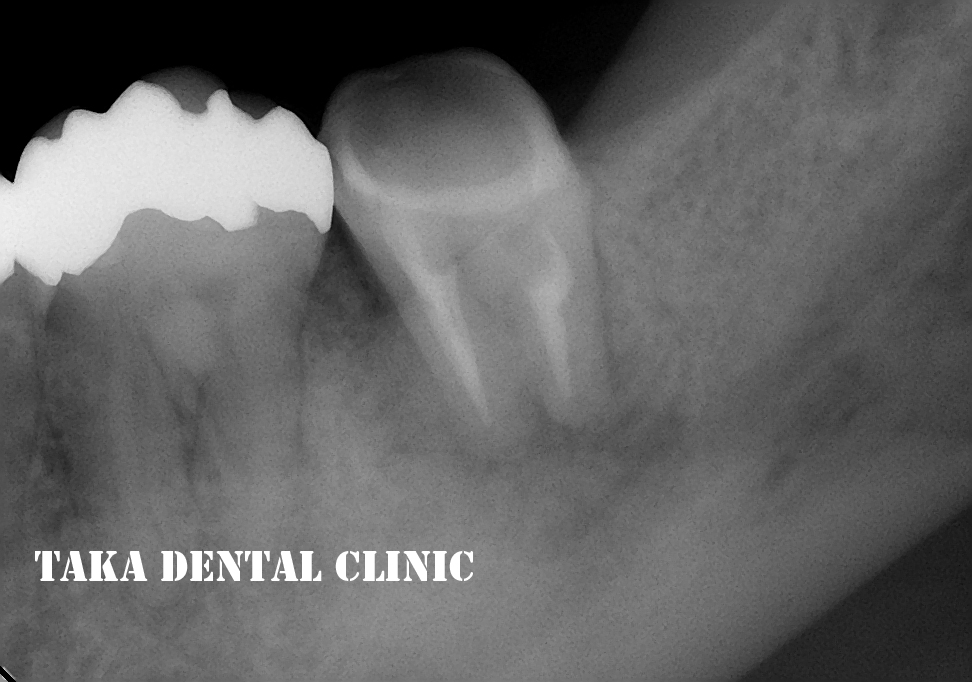

そして、1年後・・・

根の病気もほとんど消失して(根の周りの黒影がなくなっています)、痛みや咬んだ時の違和感も全く無いそうです。